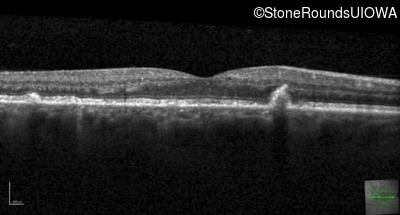

Optical Coherence Tomography - Left - 20/32 sc

Exemplar / OCT Stack

OCT Stack